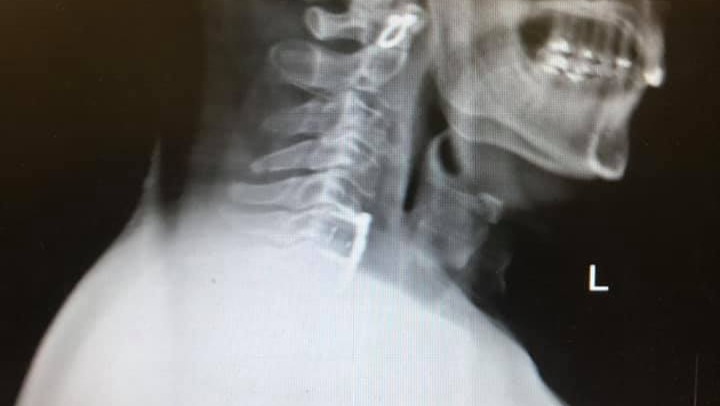

Hi All, my name is Kirsten and I live in Fort Wayne, Indiana. In early 2020 my dad John was riding his motorcycle in Key West, Florida where lives, and he went to stop and say hello to a friend he spotted but little did he know that a construction crew had left a 9" hole in the road partially uncovered exactly where he was about to put his foot down. This construction oversight caused him to lose balance and try to catch himself while his 700lb. touring bike to landed on top of him. He's undergone neck, back, knee, and elbow surgeries and still has more to go. Everything is also a bit more complicated for him because he lives on a boat by himself, aside from his best mate, his cat Mate.

I’ve been the helper most of my life! My life was flipped 180 with a motorcycle accident going zero mph and no one else involved. Had back, neck, left elbow n right knee. More needed ASAP but I’m tapped out.